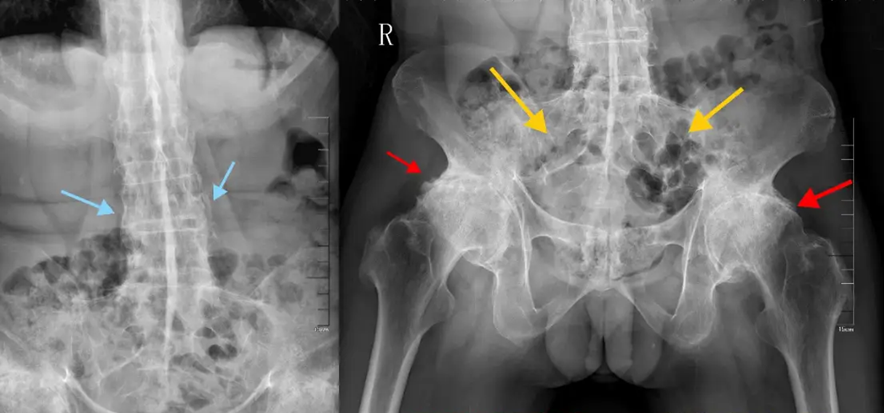

“Bệnh thường tấn công các khớp ở cột sống, khớp cùng – chậu, và hông. Khi tiến triển nặng, cột sống có thể dính cứng như một cây tre, khiến người bệnh không thể cúi, ngửa hay xoay lưng”, bác sĩ Vạn cho biết.

Cột sống của bệnh nhân bị viêm cột sống dính khớp có những thay đổi “giống như cây tre”